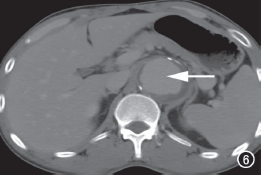

MDCT动脉造影:左主干、前降支近中段、回旋支、右冠状动脉开口部及第二转折处管壁弥漫软斑块,多发中到重度狭窄改变;主动脉及头臂动脉管壁广泛不规则增厚,管腔不规则,主动脉全程管径增宽,以降主动脉下段、腹主动脉为著,内可见附壁血栓形成(图5、6)。

图6 降主动脉管径增宽,管壁增厚,管腔不规则(箭)。